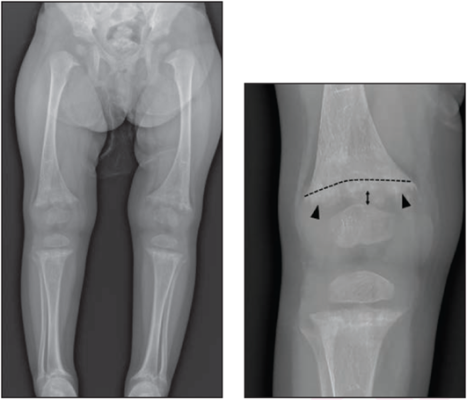

21-month-old girl with rickets and vitamin D level of 5 ng/mL. Left: Long-leg bilateral lower extremity radiograph. Right: Edited radiograph of right knee shows cupping (curved dotted line), fraying (arrowheads), and increased physeal widening (double head arrow) in distal femur, with similar findings in proximal tibia and fibula (not annotated), all consistent with rickets; radiograph shows no signs of CML. All eight radiologists correctly interpreted radiograph as showing rickets with moderate or high confidence.

Noting both high interobserver agreement and diagnostic performance for differentiating the two entities in this 7-center study, “recognition that CMLs mostly occur in children younger than 6 months and are unusual in children older than 1 year may assist interpretations,” wrote corresponding author Boaz Karmazyn from the Riley Hospital for Children in Indianapolis, IN.

Karmazyn and colleagues’ retrospective study included children younger than 2 years old who underwent knee radiographs from January 2017 to December 2018 and who either had rickets (25-hydroxy vitamin D <20 ng/mL and abnormal knee radiographs) or knee CMLs and a diagnosis of child abuse from a pediatrician. Eight radiologists independently interpreted radiographs for rickets or CML diagnoses, rating confidence levels and logging associated radiographic signs.

Ultimately, children with CML were younger than children with rickets (3.9% vs 65.7% >1 year old). The rate of false-positive moderate or high-confidence interpretations was 0.6% for CML and 1.6% for rickets. Only a single child with CML and low vitamin D received an interpretation of combined CML and rickets.

Reiterating that less- and more-experienced pediatric and non-pediatric radiologists had high diagnostic performance in differentiating rickets and CML—regardless of the presence of vitamin D deficiency, with few false-positive interpretations for these diagnoses—"findings suggestive of both rickets and CML should be viewed as indeterminate,” the authors of this AJR article concluded.